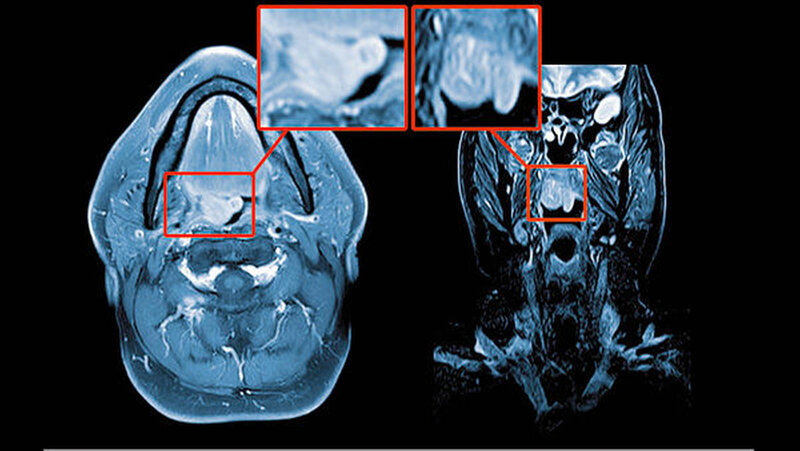

Die endoskopische Untersuchung wie auch die MRT-Untersuchung (Abbildung 1) bestätigten den Verdacht auf eine benigne, im Bereich des weichen Gaumens rechts lokalisierte Neoplasie.

Die präoperative, nicht invasive Diagnostik ist schwierig und nur mittels Magnetresonanztomogramm sinnvoll möglich. Hier zeigen die Tumore eine geringe Hyperintensität und Isointensität in der T1- und in der T2-Wichtung bei insgesamt homogener Signalintensität der glatt begrenzten Raumforderung ohne Infiltration des umgebenden Gewebes. Als Methode zur Diagnosesicherung vor Therapie kommt die Feinnadel- oder die Skalpellbiopsie infrage [Bertholf et al., 1988; McGregor et al., 2003].